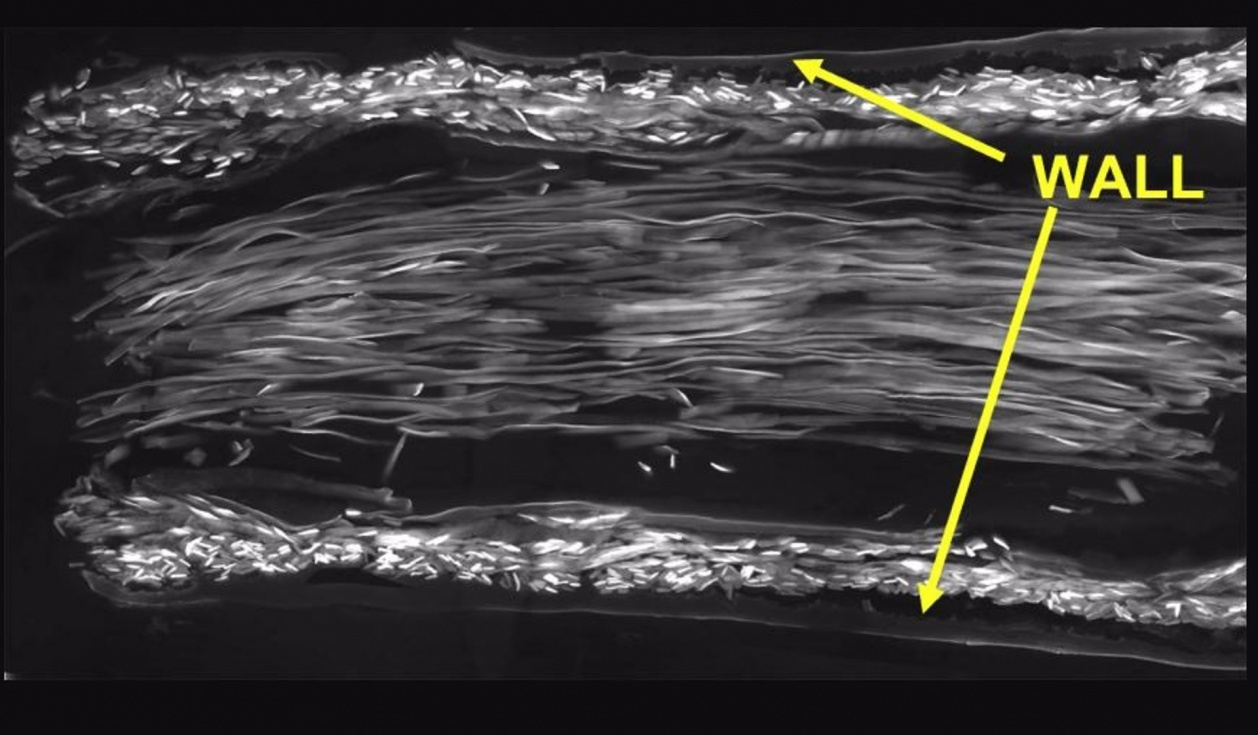

En este nuevo estudio, el equipo de investigación desarrolló un nuevo tipo de guía nerviosa utilizando dos tipos diferentes de seda natural. La pared del tubo se fabricó con seda producida por gusanos de seda (Bombyx mori), y el interior se llenó con fibras de seda de dragalinas (un tipo de seda) de telarañas doradas (Trichonephila edulis). Los tubos se probaron en ratas a las que se les había cortado el nervio ciático derecho, creando un espacio de 10 mm (una longitud significativa para una rata).

El equipo de investigación utilizó técnicas de microscopía avanzadas para analizar el proceso de curación en detalle. Esto mostró que los tubos de seda tenían una estructura altamente porosa; una característica esencial para la regeneración nerviosa, ya que permite el intercambio de nutrientes y materiales de desecho. Además, las células de Schwann, los impulsores clave de la regeneración de los nervios periféricos, se adhirieron fuertemente tanto a las paredes del tubo como a las fibras de seda de la línea de arrastre y migraron a una velocidad notable (más de 1,1 mm por día).